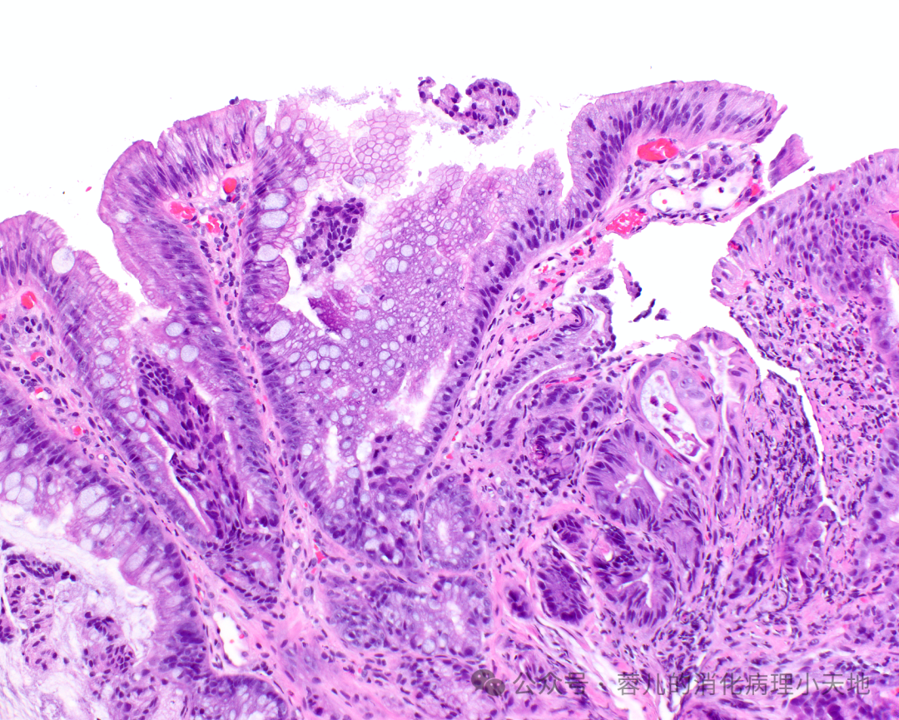

不完全肠上皮化生:由杯状细胞组成,中间夹杂着缺乏吸收细胞的胃小凹型细胞,显示刷状缘

形成病变的胃异型增生(肠型腺瘤)具有肠型表型,表现为密集的腺体,由深染的肿瘤细胞排列而成,累及胃窦黏膜

病变细胞缺乏粘蛋白,并含有铅笔状假复层核,这些核保持与基底膜的关系